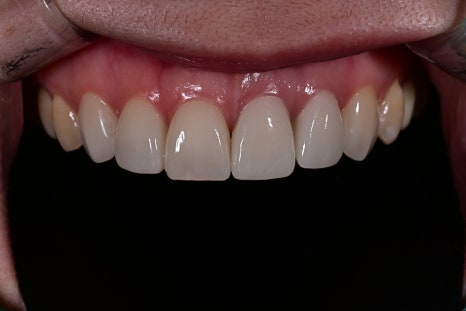

치료 전, 후 비교

<BEFORE>

<AFTER>

환자분은 가장 먼저 색의 자연스러움을 이야기하셨습니다.

기존 크라운은 주변 치아 대비 밝기 차이가 있어

‘덧씌운 티’가 난다고 표현하셨는데,

새로 디자인한 오브제로는 맨 얼굴에서도

어색함이 없고 자기 치아 같은 느낌이라고

평가해주셨습니다.

또한 절단면의 자연스러운 투명도와 볼륨감이 생기며,

웃을 때 입술 라인과 어울리는 조화가

크게 개선되었습니다.

사진 촬영 시에도 더 자연스럽게 보인다 말씀하셨습니다.